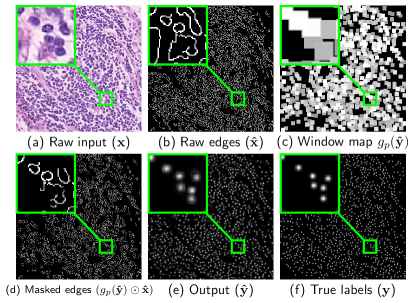

For each dataset, multiple training images are analyzed by a medical expert to hand label the nuclei boundaries. A set of representative shapes is then hand crafted by the medical expert to form the set . Some examples of the nucleus shape priors are shown in Fig. 1. These are corresponding to colon tissue images – detailed explanation is provided in Section IV. To construct a meaningful regularization term emphasizing shape priors, we need the nucleus boundary information of the input raw image . We employ the widely used Canny edge detection222Note we select Canny edge detection filter because of its simplicity and efficiency. Although its performance satisfies our intentions, other edge detection methods can also be used. filter [33] to generate the raw edge image with edges labeled as and background as , as shown in Fig. 3-(b). Note that the raw edge image is only used during the training process.

1.

The CNN output is first thresholded by to eliminate the background noise (Fig. 3-(e)) and then max pooled by with stride of 1 and the ‘SAME’ padding scheme333Because there is no change in the image grid, this is similar to the box-filtering operation in image processing.. This results in a window map that has window centered at each location within the soft detected region (Fig. 3-(c)). As expected, a window with higher numerical value will result if the detected label values (in ) are correspondingly higher (closer to 1).

2.

The window map is then multiplied with the raw edge image element-wise. This step serves to mask out the edges from that surround the detected location in , as shown in Fig. 3-(d).

-

3.

The masked edge image is convolved with the shape priors in set to generate a measurement of how well does the detection fit inside the nucleus shape. If has more labels predicted inside the nucleus boundary, Eq. (2) will achieve a smaller value (more negative).